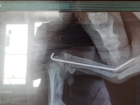

«Врач пытался сохранить кость»: в клинике Волжского прокомментировали историю с ампутацией лапы шпицу 26.07.2022 Общество -

«Через 3 дня собака бы умерла», - хозяйка об ампутации лапы после лечения в клинике Волжского 25.07.2022 Общество